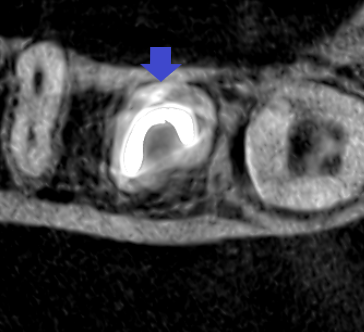

下顎第二大臼歯の初診時の水平断のCT画像です。歯根は雨樋状をしており、根管は黒い2根管しか清掃されていません。樋状根は、根管清掃も雨樋状の清掃が必要です。

下顎第二大臼歯の根管充填の水平断のCT画像です。雨樋状に根管清掃・根管充填できています。根管充填時には、全ての痛みは消失していました。